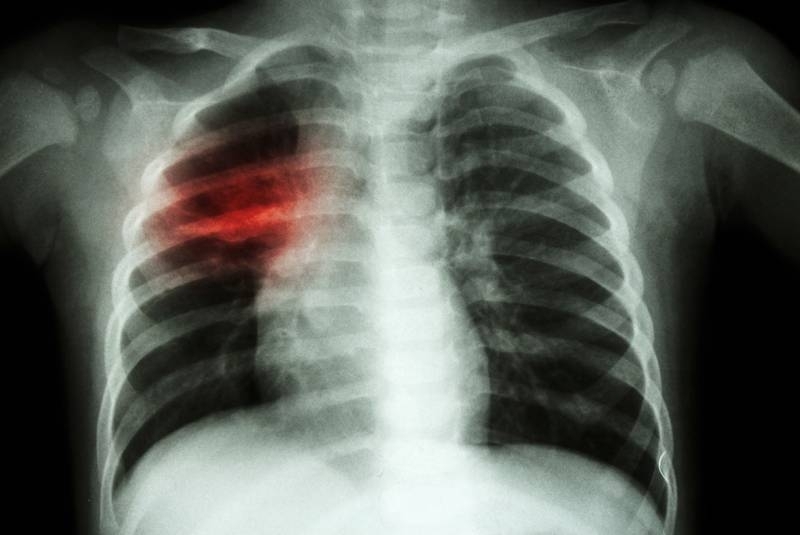

Новите случаи на туберкулоза по света са се увеличили за

...... г. туберкулозата е била на първо място в света по инфекциозни заболявания, но от 2020 г. е на второ място след КОВИД-19 и преди СПИН.

Броят на хората заразени с туберкулоза включително резистентната към лекарства

Рязко се увеличават болните с туберкулоза За това алармира в

Бум на болни от туберкулоза е отчетен във Врачанско сочи